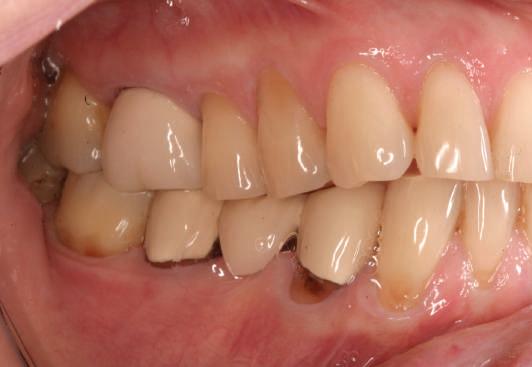

Conform informațiilor oferite de CBCT, pe pozițiile molarilor 36 și 37 au fost inserate două implanturi Ankylos (Dentsply Implants) C/X A 11 (diametru 3.5 mm, lungime 11 mm).

Datorită stabilității primare la inserare de aproximativ 35 Ncm pentru ambele implanturi, am optat pentru înșurubarea bonturilor intermediare conice Balance Base Narrow Straight GH 3.0 și vindecare transgingivală (fig. 2, 3). Inserarea acestor stâlpi s-a realizat la un cuplu de forțe de 25Ncm, cu ajutorul unei chei dinamometrice, aplicându-se ulterior cape de protecție (fig. 4). Vindecarea transgingivală postoperatorie a decurs fără complicații.

Figurile 1. Status clinic şi radiologic iniţial; 2. Bontul Balance Base Narrow Straight GH 3.0; 3. Bonturile Balance Base Narrow aplicate imediat post-inserare la 25 Ncm; 4. Aplicarea capelor de protecţie şi sutura; 5. Stâlpii de amprentă înşurubaţi la nivelul bonturilor Balance Base Narrow;